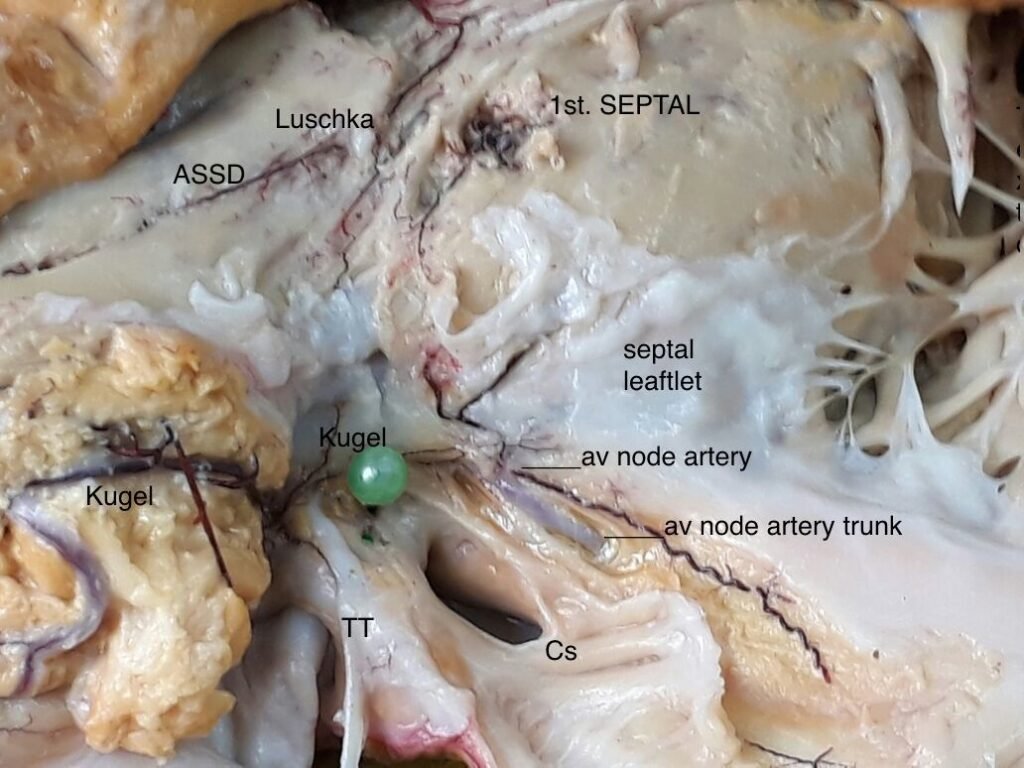

En las siguientes fotografías se ilustran las cuatro fuentes vasculares del nodo atrioventricular.

Dos son conocidas hace décadas, las últimas dos demostradas por nuestro laboratorio hace un par de décadas. Son -estas últimas- la arteria anastomótica auricularis magna o arteria de kugel y la arteria septal derecha.

Ambos vasos se ilustra cómo llegan al sistema de conducción.

Detalle de la fotografía 3 con las referencias.